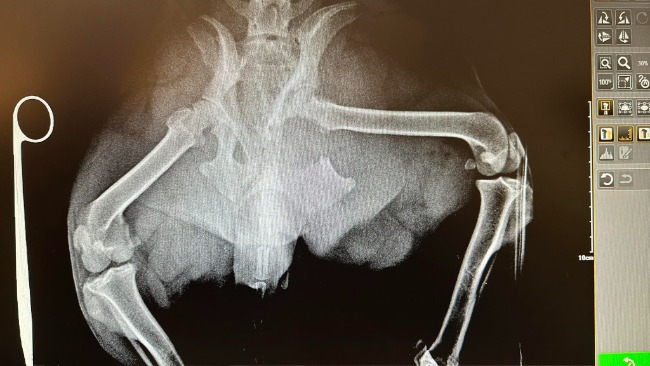

Jestem Klaudia i od ponad 3 lat jestem właścicielką suczki o imieniu Zoja. Jest to bardzo energiczny i przyjazny piesek. Niestety w niedzielę doszło do wypadku, w którym doszło do licznych złamań kości. Złamania miednicy z lewej strony. Pęknięcie kości kulszowej z przemieszczeniem. Złamanie kości łonowej. Oraz jest też podejrzenie pęknięcia spojenia krzyżowo-biodrowego.

Okazało się że trzeba było zoperować obie nogi . Ma poskręcane kości tytanowymi śrubami, które zostaną z nią do końca życia ale będzie żyła . A to najważniejsze ❤️